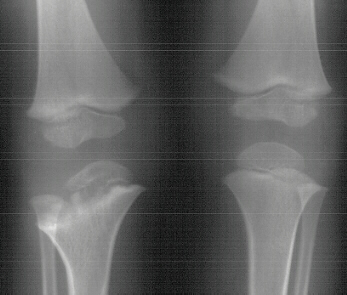

deformity of the metaphyseal region. By age 11 the child had a

good gait pattern however the upper extremity length discrepancy

was becoming a cosmetic and functional concern. X-rays at age

11 show significant angulation developed in the humerus(image

3,4 & 5). However tibial growth was good.